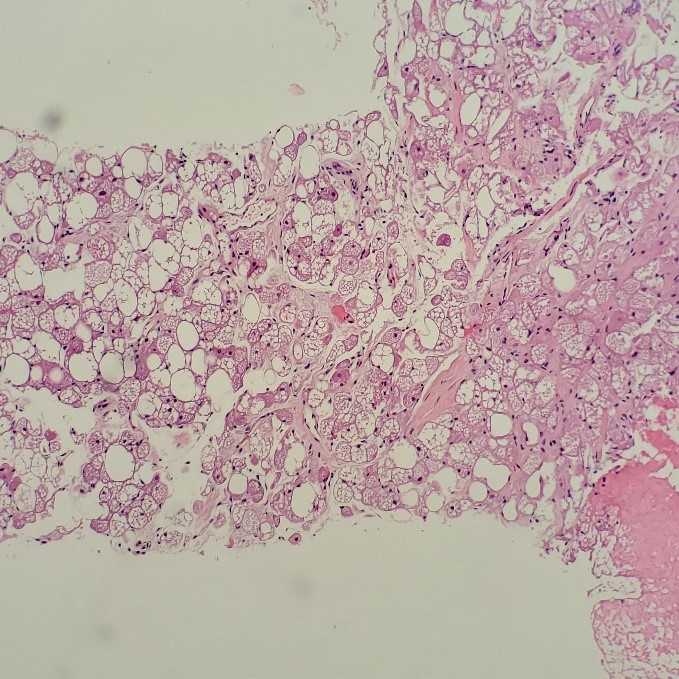

What non-heme surprise is THIS?! Are these histiocytes? There’s no way, those nucleoli are aggressive! Look at the chromocenters! The variation in nuclear size! What epithelial beauty is this? Is it epithelial?! Is that a fibrovascular core? It can’t be sarcomatoid, could it? Twenty inner monologue questions later, “okay, it’s adequate,” I said to the radiologist. But wait… should I do it? Should I press for a core biopsy? The radiologist asked me if I needed anything else for the diagnosis. Perhaps she saw my puzzled expression, compelling her to tell me that she felt the imaging looked weird – she thought it wasn’t a heme case either. At least I’m not alone here. I took a deep breath, expecting the worst and hoping for the best, and I asked the radiologist to collect a core biopsy. She checked the ultrasound Doppler for excessive vascularity, and much to my surprise, she agreed to perform the core. After collecting more FNAs for my cell block and dropping the core biopsies off in surgical pathology, I showed the case to my attending pathologist. He also agreed that we don’t need to triage it for heme. He asked if the patient had any significant history other than PV, splenic lesions, and brain mets, and I told him nothing was reported in his chart. I checked the chart again for good measure while he was running through his differential diagnoses of lung, GI, prostate, etc., and saw the patient was scheduled to see dermatology later that week. I mentioned to that to my attending, and he suggested it could be a melanoma.

The following morning, I examined the pap-stained slide and began to second guess myself. Was I wrong? Could it be a heme case? Hodgkin’s wasn’t in the differential, and these cells look so much more aggressive than Reed-Sternberg cells. At least we have a core biopsy either way. We could run immunos on the cell block and save the cores for molecular. I screened the pap-stained slides a little longer, focusing on the macronucleoli, the owl-eye and eccentric nuclei, the poorly-differentiated nature of this… MELANOMA. YES! So, the cells might not contain any melanin pigment, but my attending’s inkling was exactly right. Waiting for my cell block to arrive, I listed melanoma as my primary diagnosis with a differential of lung or prostate cancer.

The cell block confirmed my non-heme diagnosis and kept my differentials at bay. The attending pathologist ordered an immunohistochemistry profile of S100, HMB-45, and Melan A, as well as AE1/AE3. The first three immunostains (prior to our adoption of SOX-10) confirmed a diagnosis of metastatic malignant melanoma. Soon thereafter, the patient’s primary lesion was identified on his back, and he was treated with radiation and immunotherapy. Unfortunately, the metastases were not responding to the immunotherapy, and a few days after a clinical trial was offered, the patient passed away.

Melanoma is known as the great mimicker, especially in amelanotic form, and it should always be in the back of your mind as a differential diagnosis. Lack of melanin pigment and a large cherry red macronucleoli leads us to favor lung, prostate, or serous adenocarcinoma), renal cell carcinoma, hepatocellular carcinoma, Hodgkin’s lymphoma, or even an epithelioid sarcoma. This case highlights the need to remember that metastatic melanoma is always a possibility, even when you do not have a primary site or previous clinical history of the disease.